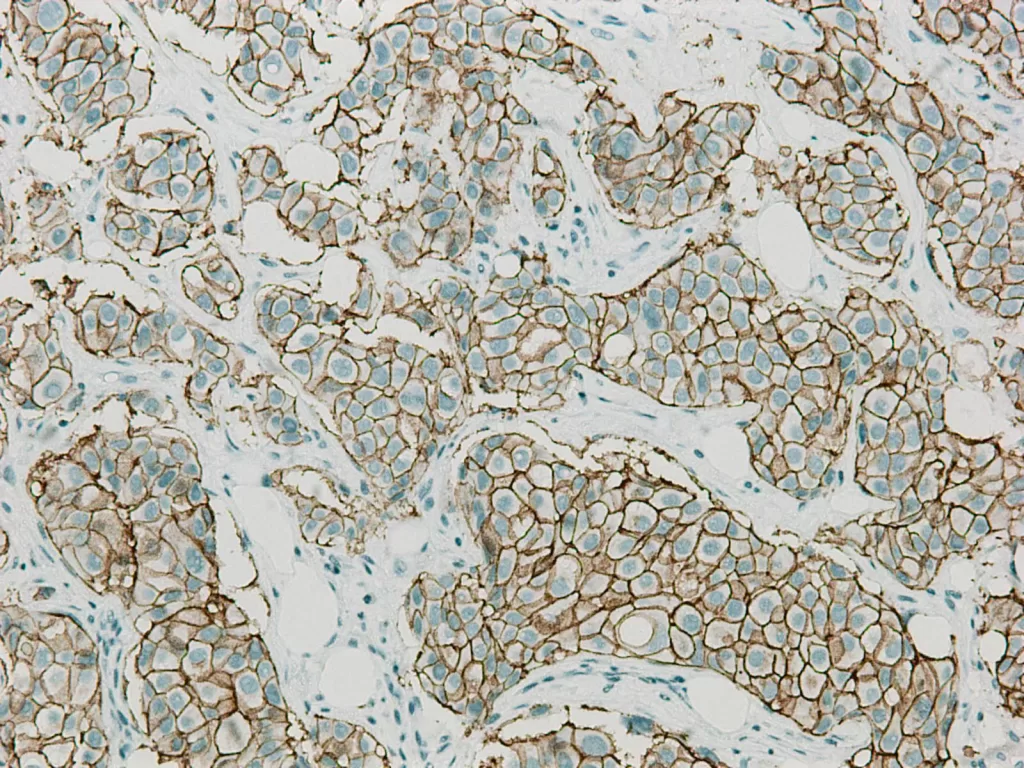

Her2(人類表皮生長因子受體 2):若它過度表現,癌細胞就像踩下油門,不斷加速、無法停下。但現代醫學已能找到專屬的煞車,以標靶藥物精準鎖定這個訊號。

當妳做完乳房攝影或超音波,那一小片被切下的組織會進入顯微鏡的世界。病理醫師在那裡看見平常看不見的部分,那些色彩、結構與節奏,試著從中解讀身體的語言。最後的病理報告不僅僅是診斷,更是傳達了妳的身體在說什麼、帶來了怎麼樣的希望。